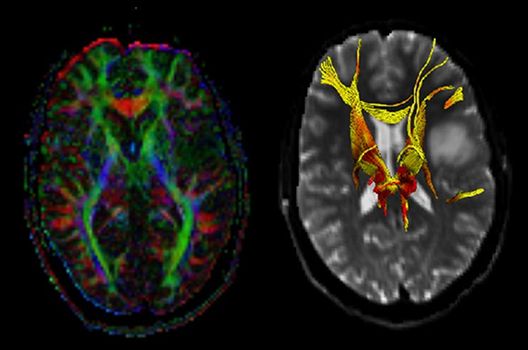

Magnetresonanztomographie

- Hochaufgelöste MR-Bildgebung (HR-MRT)

- Arterielle und venöse Angio-MRT

- MR-Protonenspektroskopie

- Funktionelle Bildgebung des Gehirns (fMRT)

- MR-Diffusionstensorbildgebung (Faserbahndarstellung/fiber tracking)

Die Schwerpunkte in der MR-Forschung liegen in der multiparametrischen und funktionellen Bildgebung bei onkologischen und anderen, neuroradiologischen Fragestellungen und umfassen die Anwendung modernster MR-Verfahren sowie die Untersuchung an Hochfeld-Geräten.

Die Magnetresonanztomographie (MRT) ist ein Verfahren, bei dem durch magnetische Kräfte Bilder des Körperinneren angefertigt werden. In der Neuroradiologie können manchmal kleinste Veränderungen schwere Folgen haben; daher forschen wir an der Entwicklung hochauflösender MRT-Sequenzen, mit denen diese Prozesse und auch einzelne Nervenfaserbahnen sichtbar gemacht werden können. Darüber hinaus sind bei vielen Erkrankungen des Gehirns die Blutgefäße betroffen. Daher arbeiten wir an der Neu- und Weiterentwicklung von MRT-Sequenzen zur Darstellung der Blutgefäße und zur Blutflussanalyse (sog. „Angio-MRT“). Einen besonderen Forschungsschwerpunkt unserer Klinik stellen die MR-Protonenspektroskopie und die funktionelle MRT dar, mit denen die Analyse einzelner chemischer Substanzen im Hirngewebe oder die Darstellung ausgewählter Hirnfunktionen möglich ist.